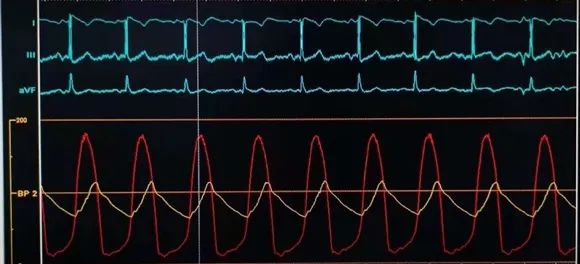

植入前后跨瓣压差

植入前压差63mmHg,植入后压差2mmHg